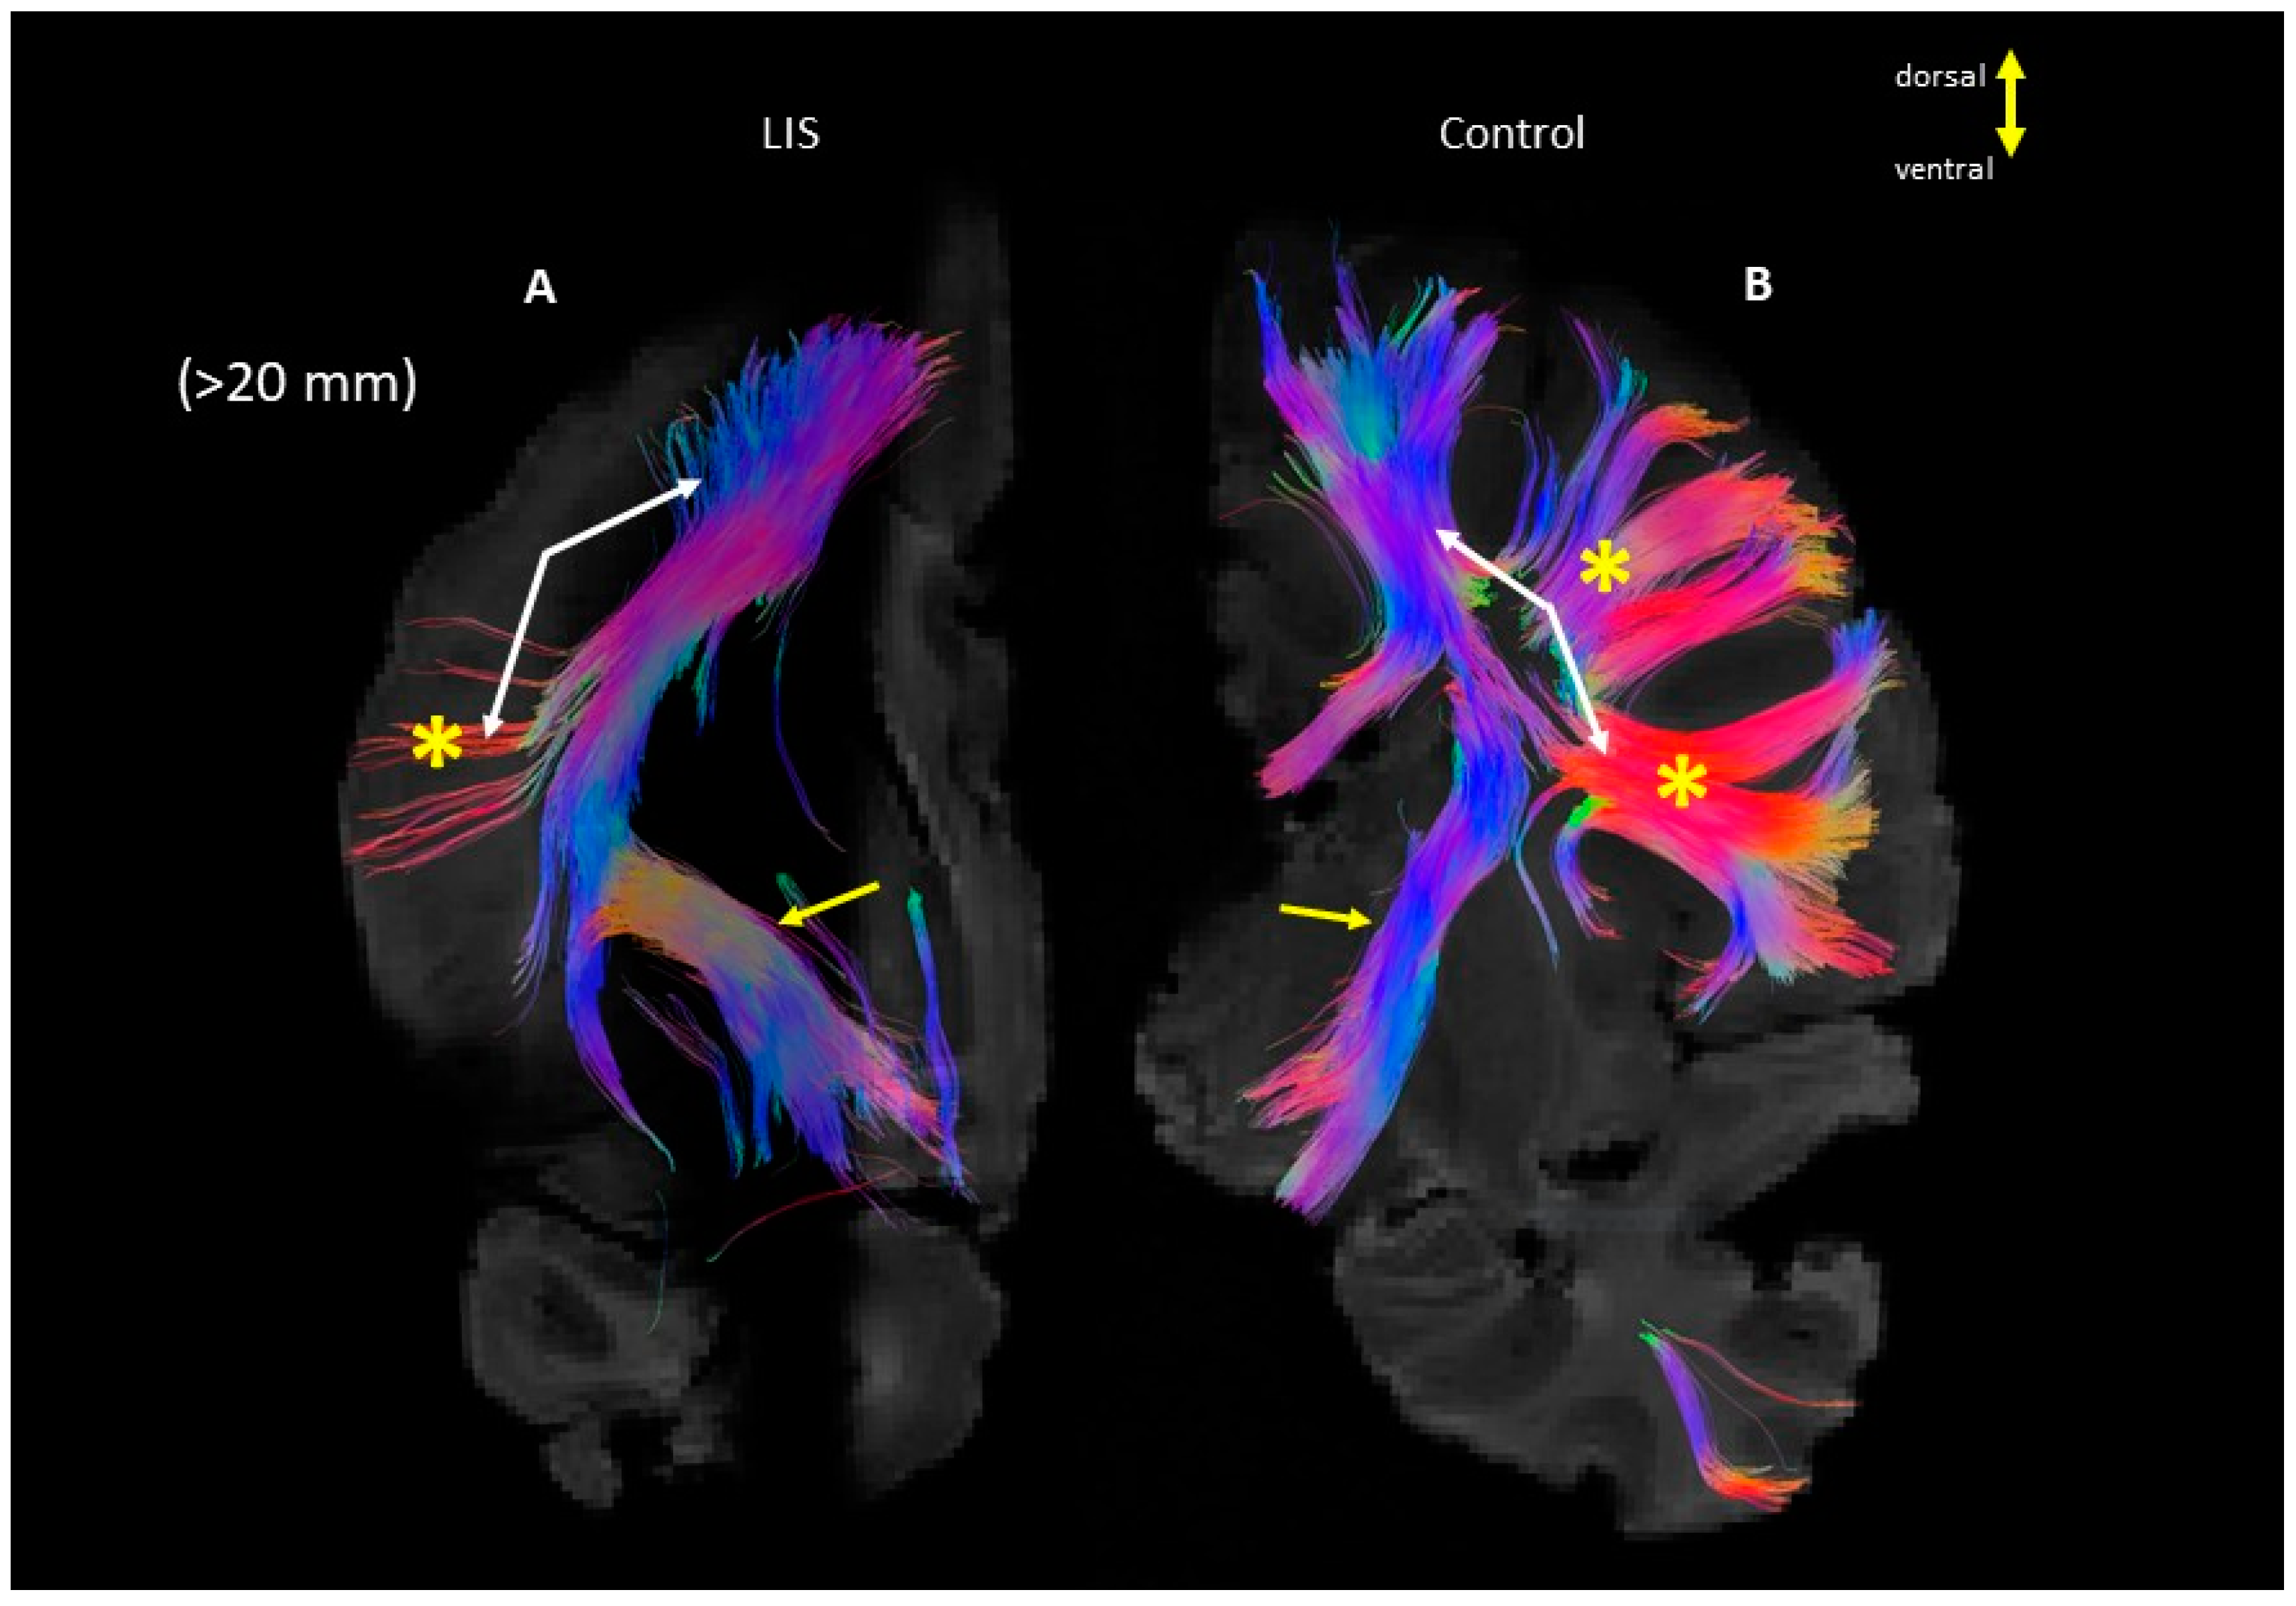

3. Results

4. Discussion

4.1. Developmental Aspect of the LIS Brains

4.2. Microanatomy of Lissencephaly